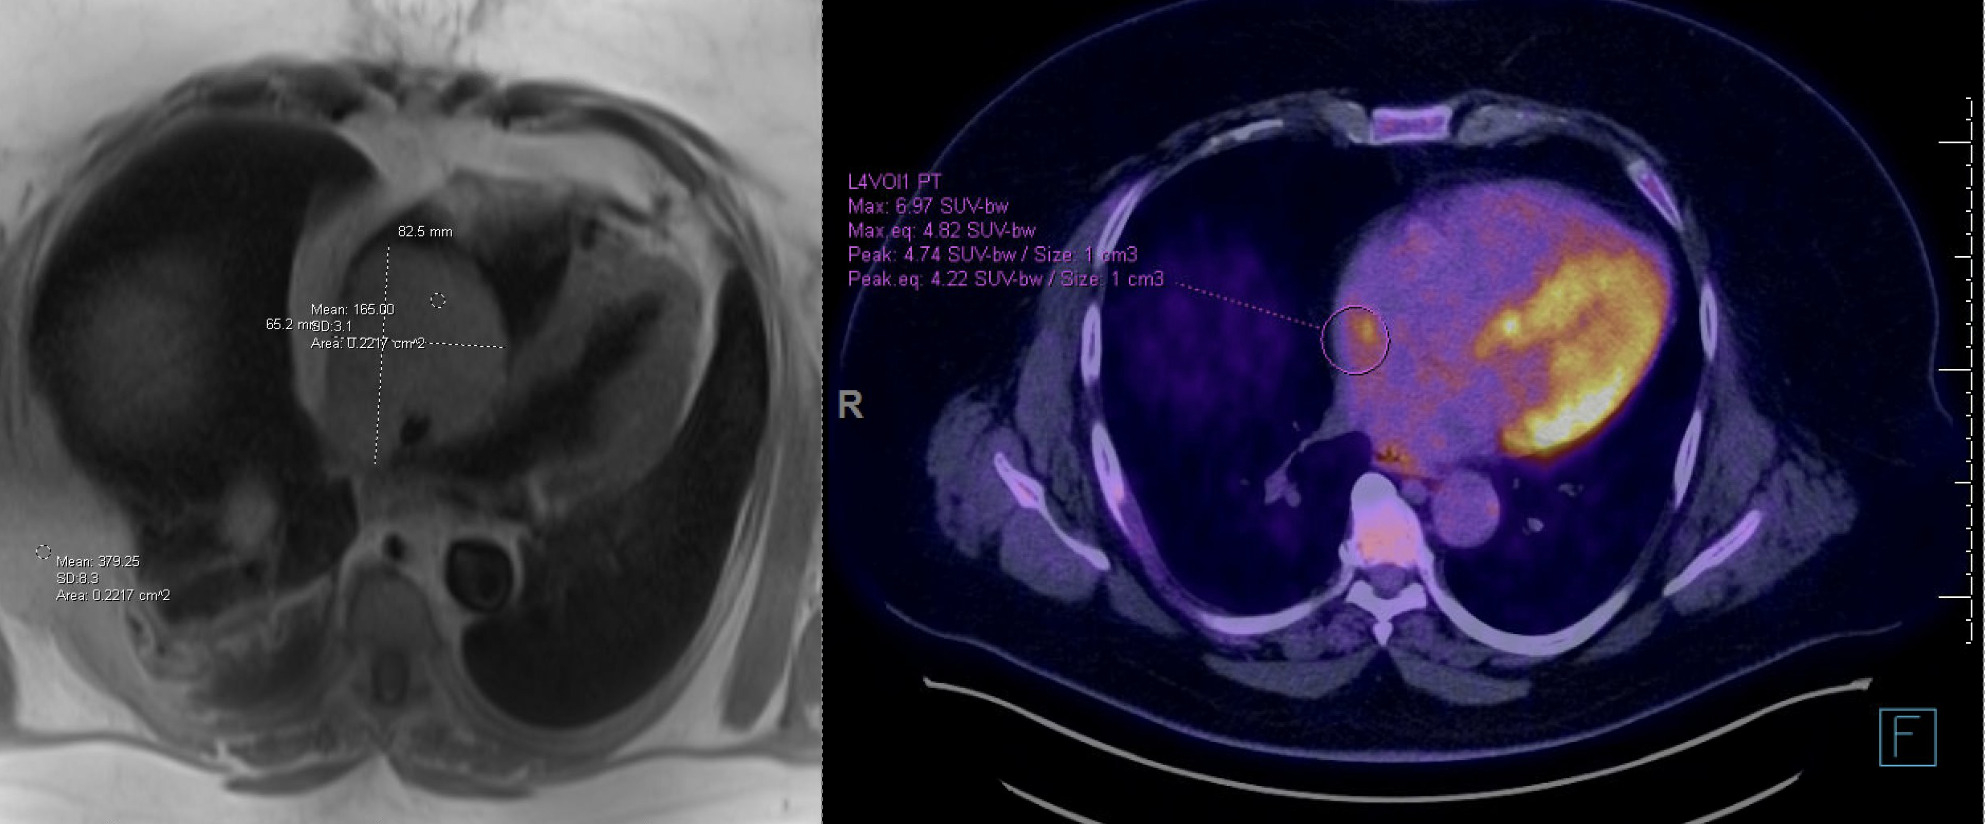

Case Presentation A 44-year-old male with well-controlled HIV on Rilpivirine presented with a 2-week history of progressive shortness of breath, facial edema, and exertional peripheral cyanosis. His physical exam confirmed facial and upper extremities edema and jugular venous distension suggestive of superior vena cava syndrome. Contrast computed tomography (CT) of the chest identified a large 12 × 6.2 × 7.5 cm lytic rib lesion invading the pleura and chest wall, accompanied by left supraclavicular, axillary, mediastinal, and upper abdominal lymphadenopathy. CT also showed a large (8.3 × 5.8 × 6.0 cm) right atrial mass causing near-complete occlusion of the superior and inferior vena cava (Fig 1A). A transthoracic echocardiogram with contrast-enhanced imaging confirmed a large right atrial mass extending into the IVC (Fig 1B). Cardiac magnetic resonance imaging (MRI) further detailed an 8.3 × 6.5 × 6.4 cm mass nearly filling the right atrium, infiltrating the interatrial septum with mass effect on left atrium and encroaching on the right superior and inferior pulmonary veins (Fig 2A). Biopsy of the rib lesion confirmed high-grade B-cell lymphoma with 11q aberration. The patient was started on Rituximab combined with E-POCH chemotherapy on day 7 of admission. A follow-up PET-CT scan after the first cycle showed significant regression of the intracardiac mass (Fig 2B.)